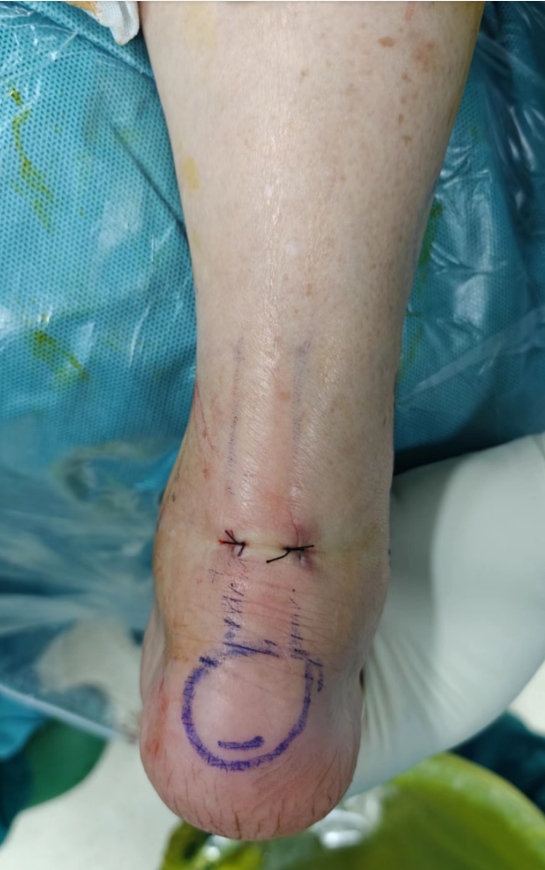

术前标记体位

术中精细操作,切除病灶

术后切口仅8毫米